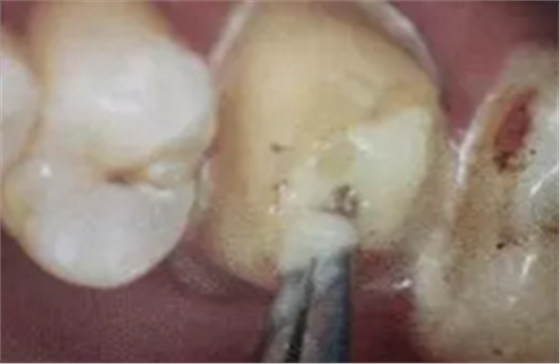

(超聲去除根管殘留物)

通常此時(shí)以超聲潔牙機(jī)更換較細(xì)工作尖進(jìn)入根管(根管消毒沖洗液配合清潔工作后面會(huì)提到),徹底去除樁道根管壁上的附著殘留物,效果明顯。再配合X線片、根管顯微鏡輔助檢查清理的情況下更佳。